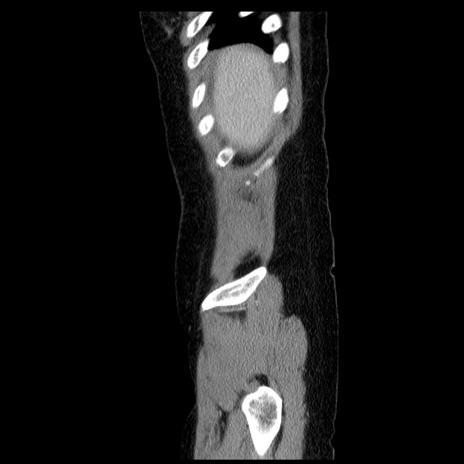

症例6(矢状断像)

【症例】50歳代女性

【主訴】下腹部痛

【既往歴】卵巣癌術後(8年前に当院で卵巣摘出)

【身体所見】 意識清明、腹部:平坦、腸蠕動音→、やや硬、下腹部自発痛・圧痛あり、反跳痛あり、筋性防御なし。

【データ】WBC 16000、CRP 0.01